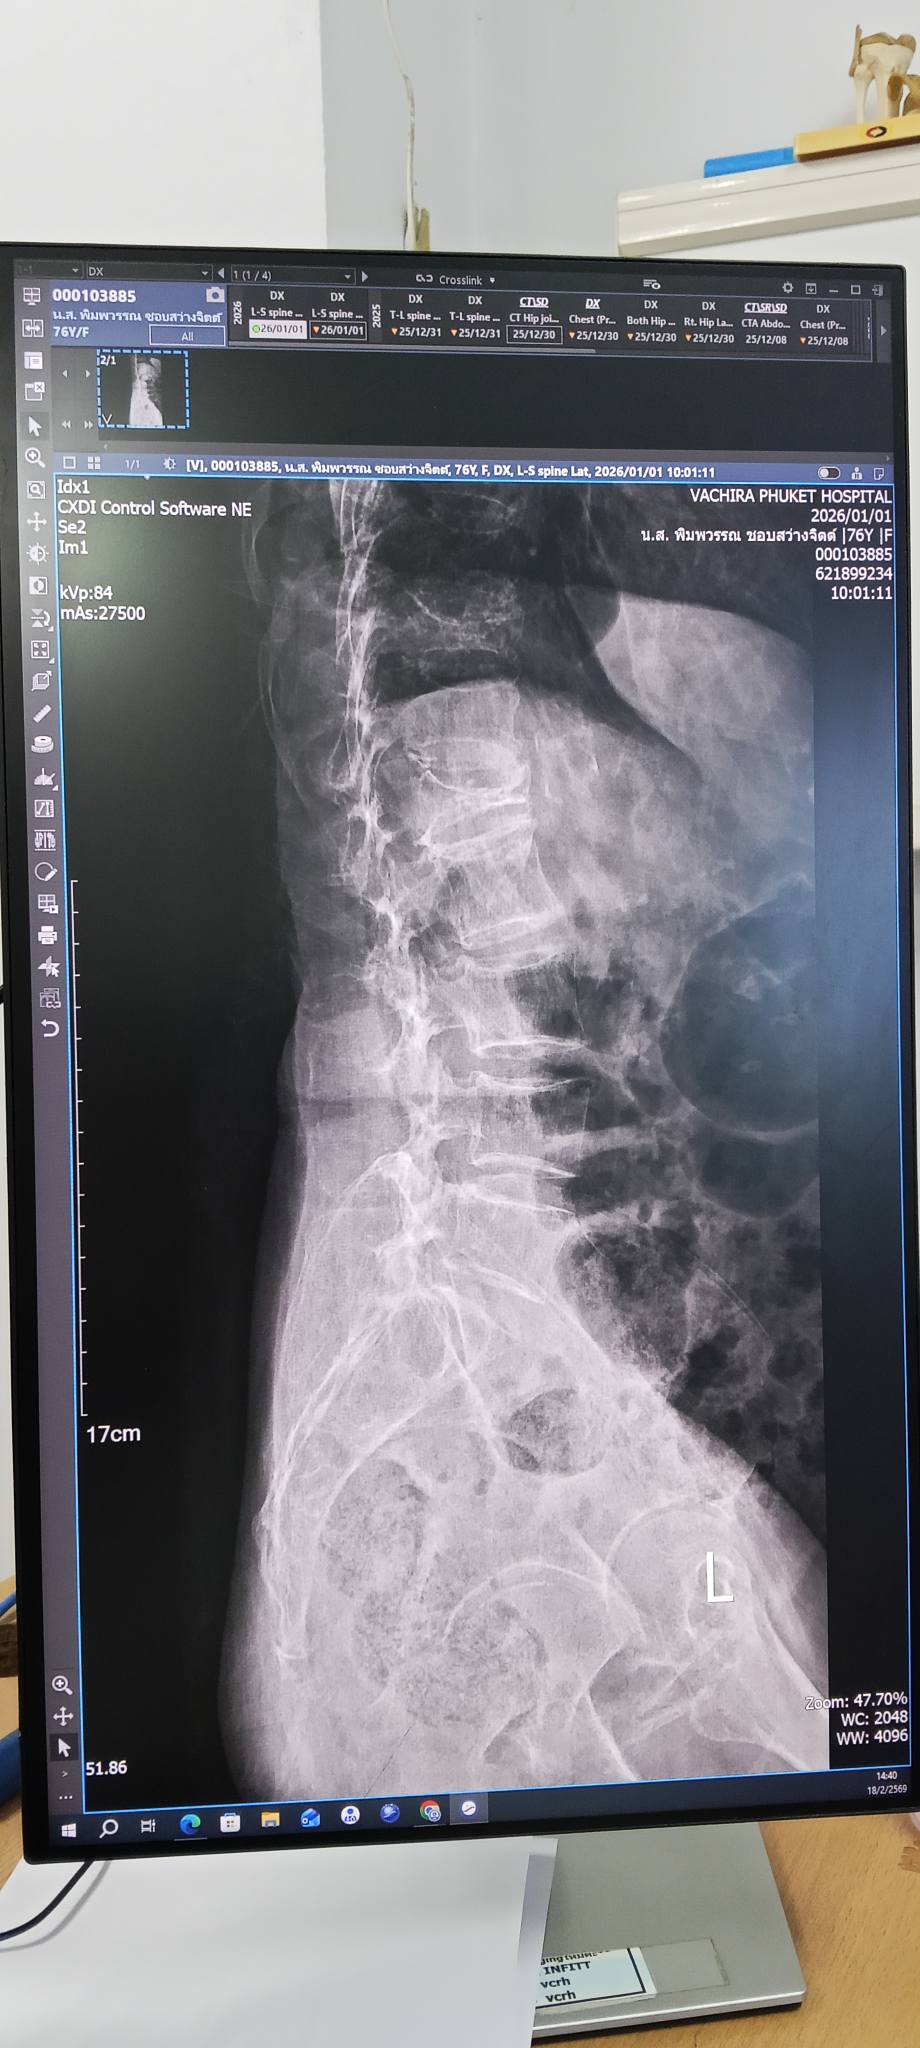

เหตุก็เพราะกระดูกสันหลัง ข้อหนึ่ง ยุบตัวไปครึ่งหนึ่ง

แกเล่าว่ามี 2559 เคยล้มแบบนี้เหมือนกันในบ้านหลังเก่า

ต้องใช้ชีวิตด้วยการนอน คลานไปมาอยู่ 4 เดือน

แต่ก่อนหน้านี้ แกเข้ารพ. ด้วยอาการเจ็บ

ล้ม ก้นกระแทกในห้องน้ำ

หมอจะผ่าตัดให้ แต่แกบอกหมอว่า ไม่ผ่าตัด